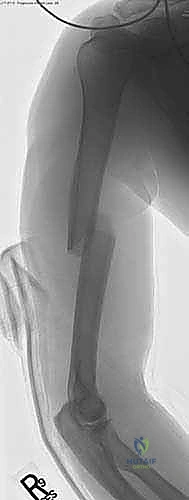

يتم إعطاء المريض تخديراً عاماً، وأحياناً يُضاف إليه تخدير موضعي للأعصاب (Nerve Block) لضمان عدم الشعور بأي ألم بعد العملية لعدة ساعات. يوضع المريض في وضعية "كرسي الشاطئ" (Beach Chair Position) المائلة، أو وضعية الاستلقاء مع إمالة الذراع، مما يتيح للدكتور هطيف وصولاً حراً للكتف واستخدام جهاز الأشعة السينية التداخلية (C-arm) بسهولة.

2. الشق الجراحي الدقيق (The Incision):

يقوم الدكتور هطيف بعمل شق جراحي صغير (لا يتجاوز 3-5 سم) في الجزء الأمامي الجانبي للكتف. يتم فصل ألياف العضلة الدالية بلطف شديد بدلاً من قطعها، مع الانتباه التام لعدم تجاوز المسافة الآمنة لحماية العصب الإبطي.

3. تحديد نقطة الدخول (Entry Point):

هذه هي الخطوة الأكثر حرجاً في الجراحة. يجب إدخال المسمار من نقطة محددة جداً أعلى عظم العضد. يفضل الدكتور هطيف إدخال المسمار من منطقة "الحديبة الكبرى" (Greater Tuberosity) أو الحافة الغضروفية، لتجنب إتلاف الغضروف المفصلي للكتف (Rotator Cuff)، مما يمنع حدوث آلام الكتف المزمنة التي كانت شائعة في التقنيات القديمة.